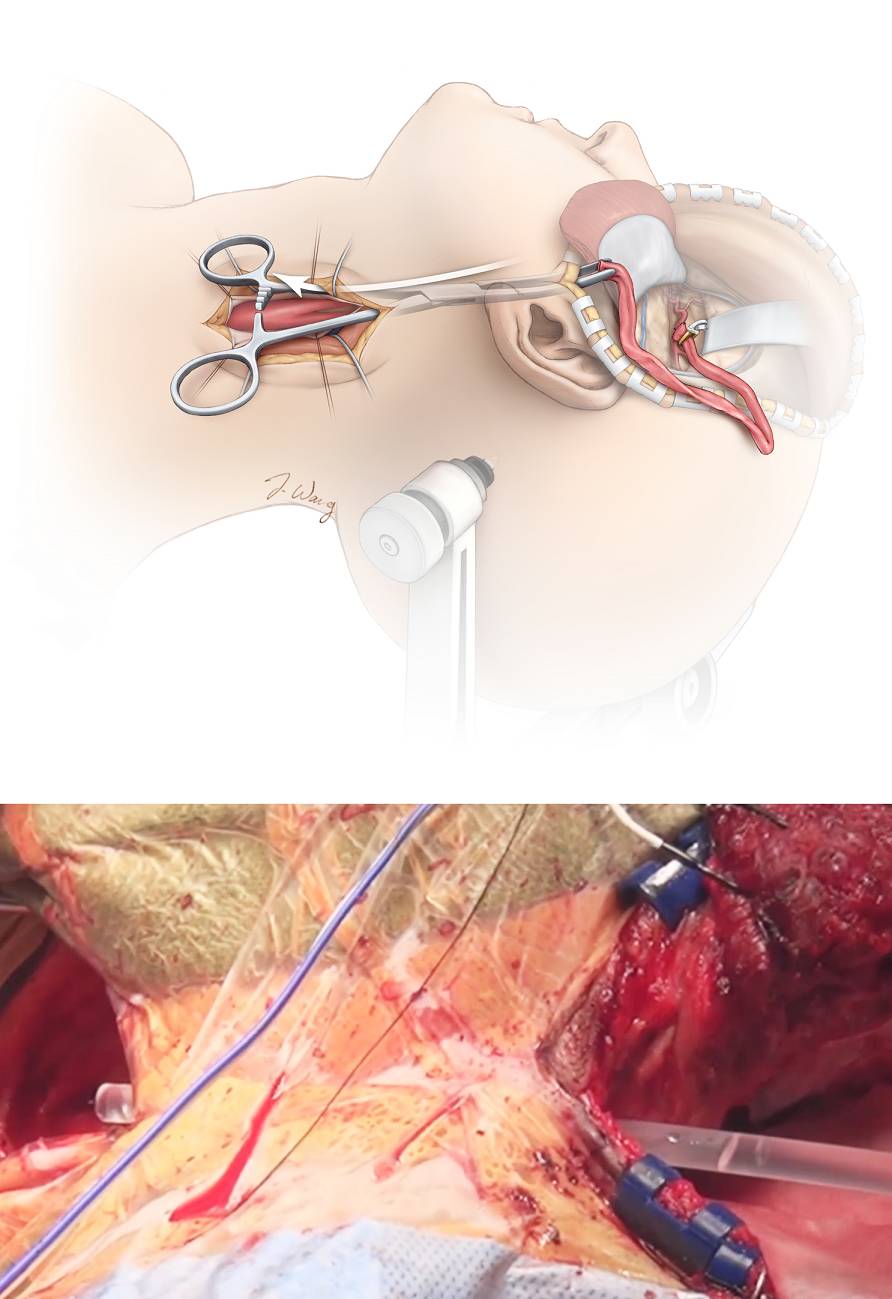

图2. 尸头标本演示使用静脉进行ECA/ICA-M2高流量搭桥。颧弓上钻一沟槽容纳桥血管无缠结地通过;在豆纹动脉远端选取一段分支最少的M2作为受血动脉临时阻断,采用端-侧吻合的方式以8-0或9-0的尼龙线间断缝合远端吻合口(右上图的箭头);随后完全阻断颈部的ICA或ECA,使用7-0尼龙线,桥血管近端可以端-侧吻合至ICA,也可以端-端吻合至ECA。(图片由AL Rhoton,Jr教授授权)

图3. 依据供血、受血动脉的位置和计划分离桥血管的部位来调整患者的体位。沿胸锁乳突肌前缘做一道5cm的切口暴露颈部的ICA和ECA。同时进行颈部解剖、开颅和取桥血管可以加快手术进程。

图4. 笔者偏好使用桡动脉。仔细分离、结扎该动脉的小分支,避免损伤主干。获取一段合适长度的桥血管并实现无张力吻合至关重要。该步骤由外周血管外科医师完成,个中细节这里不再详细论述。取得桥血管后,肝素盐水灌洗、膨胀管腔(压力扩张技术)。

接下来是将桥血管从颧弓根表面的皮下隧道拉向颈部的术区。将一把止血钳从颞肌附着处插入,朝下颌角方向,穿过咬肌和腮腺筋膜最终到达颈部切口的上端。钳子夹住一根儿童胸腔闭式引流管之后回退,这样引流管便可连接头颈部切口并能为桥血管提供稳固而平滑的通道。若计划将桥血管留置于耳前,为了避免盘曲扭结或管腔狭窄,可能需要在颧弓上磨一条沟槽。

图8. 桥血管借助儿童胸腔闭式引流管通向颈部。在此之前,先于颧弓磨一条骨槽防止血管受卡压。引流管上剪开个小裂口以允许桥血管固定于管腔内,同时,后续引导血管通过时使用该裂口定位引流管的方向和预防桥血管出现扭结。随后引流管从颈部退出,并与桥血管脱离。

与远端吻合口一样,吻合近端前同法置入橡胶垫片和引流管。修剪桥血管长度,不仅要避免过短使吻合存在张力,也要防止过长使血管扭曲打折造成血流受阻。临时夹阻断分叉处的ECA,将其远端结扎切断,再行端-端吻合。

图9. 如图示将桥血管吻合于CCA或ICA,如果这样可以减少血管扭转的话。若颈动脉分叉部太高难以企及,可以CCA为供血血管。左上图演示使用血管打孔器在CCA侧壁创造一个卵圆形的开口,右上图中清晰可见动脉造口和控制带的位置。下图为吻合完成后所见。